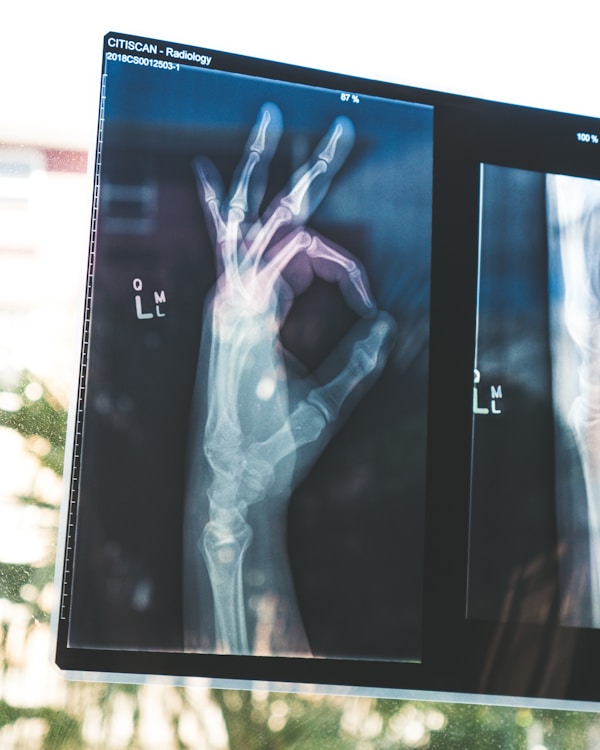

Chuyên Khoa Cơ Xương Khớp

Điều trị toàn diện các bệnh lý cơ xương khớp bằng phương pháp y học tích hợp